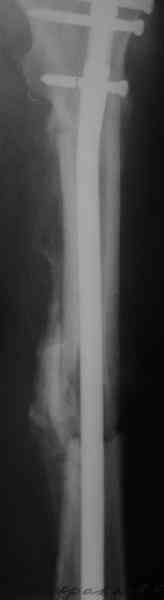

СМ> Если имеются под рукой Р-снимки, продемонстрируйте, плиз.

Вот несколько. С тисками и трубой на днях сделаем.

Саша, последний штифт, пожалуй, перегнули?

> Саша, последний штифт, пожалуй перегнули?

Там заход сделан как для прямого штифта, не через вертел.